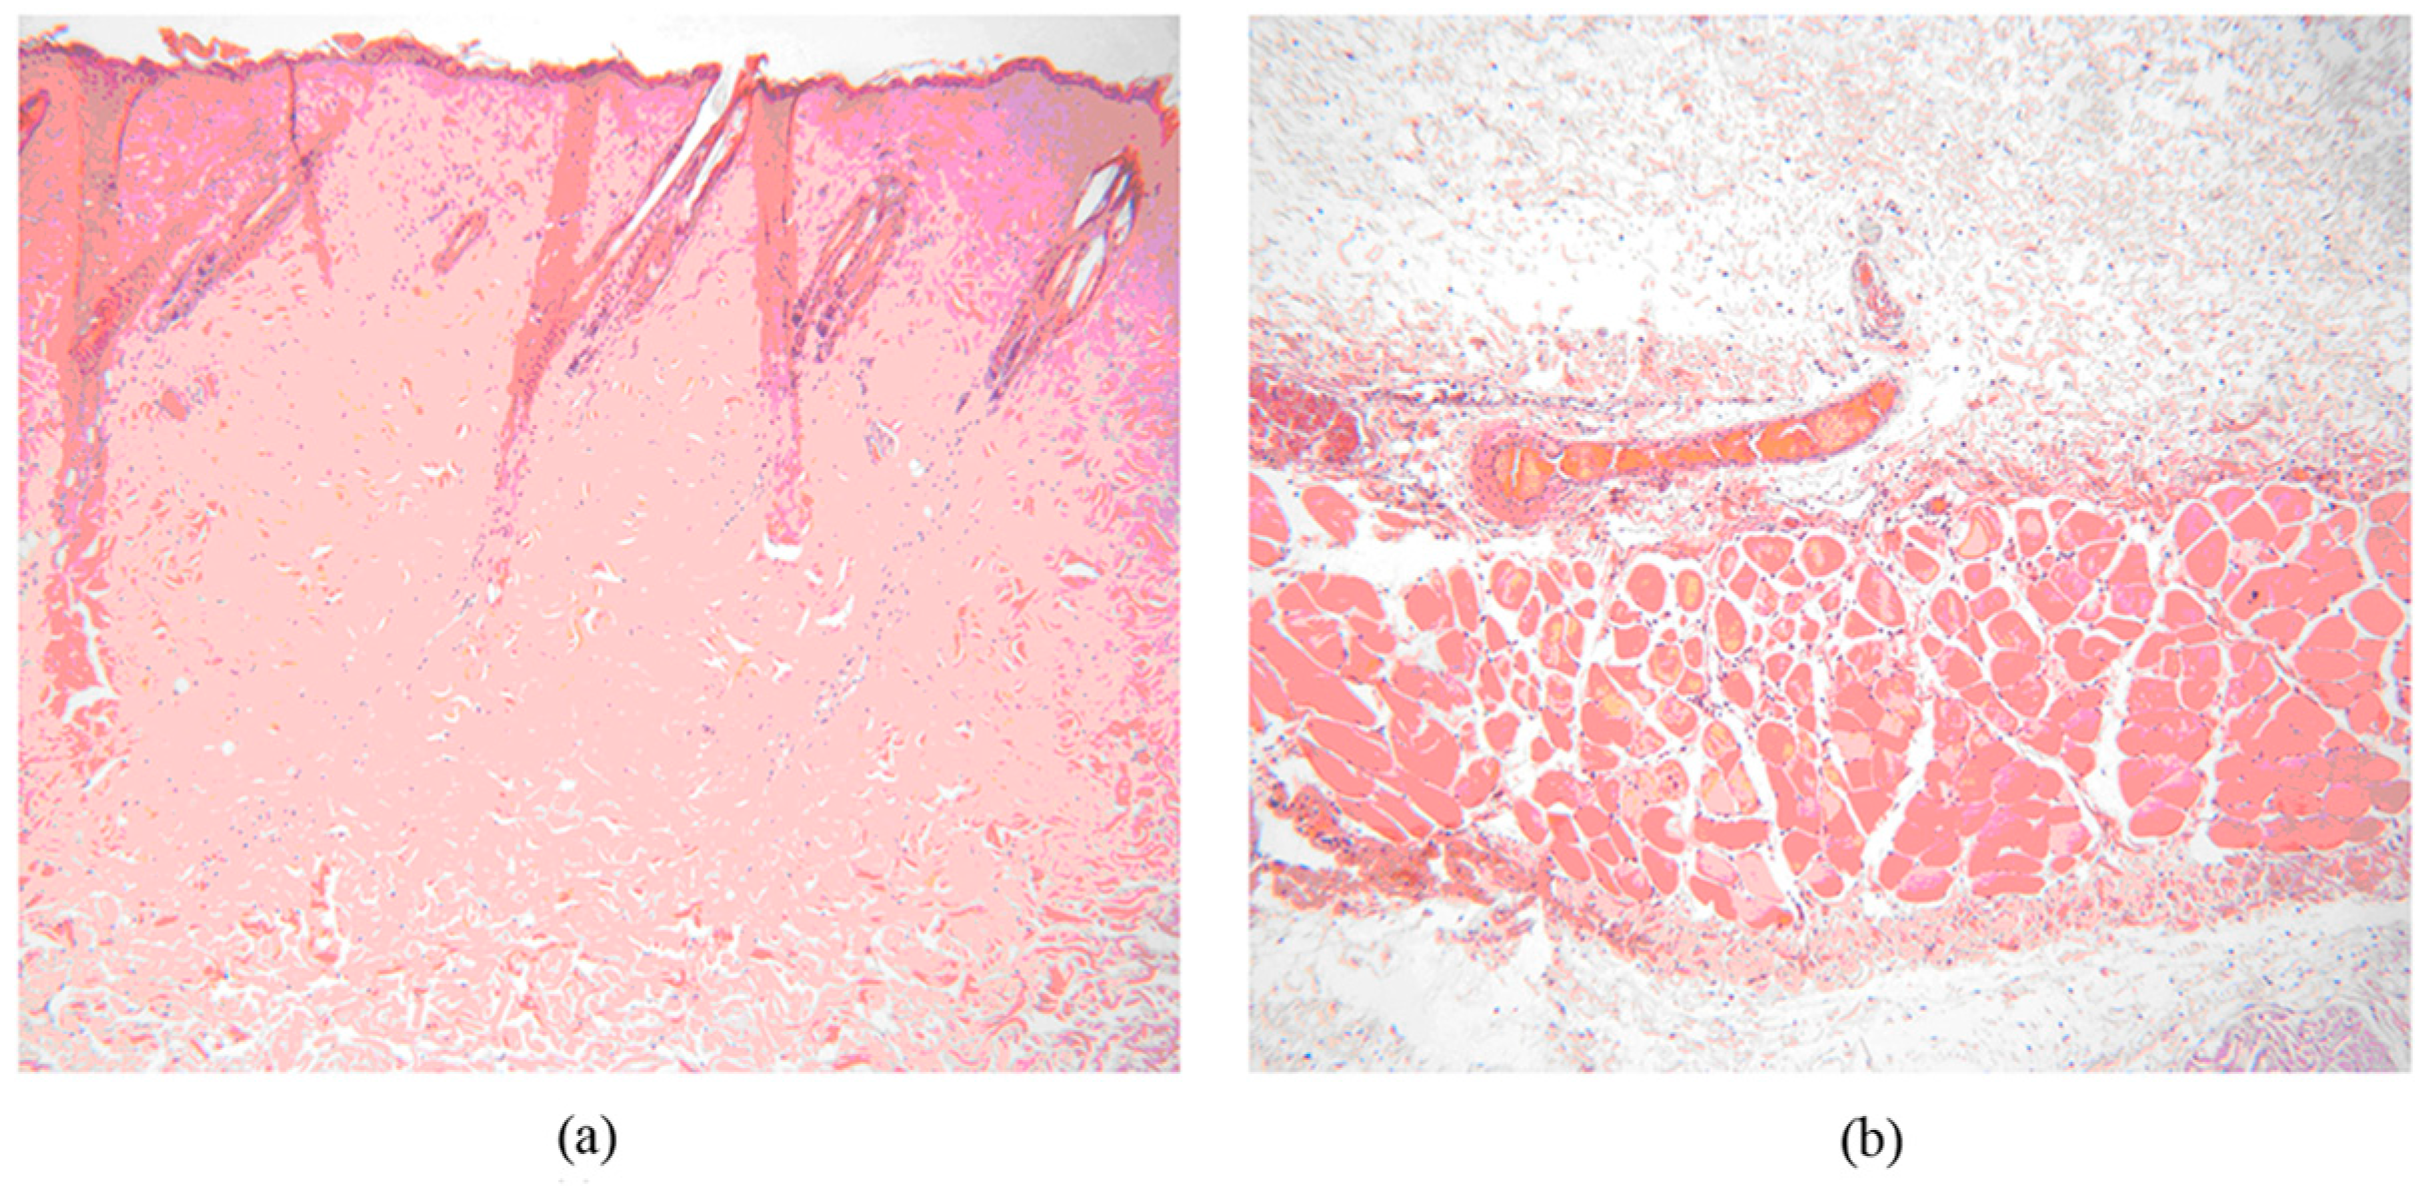

2.5.3. Histological Evaluation

3.7.4. Histological Examination